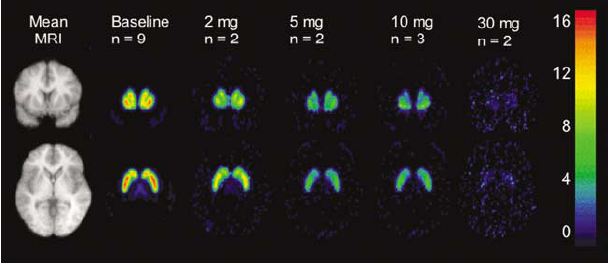

139. Meyer-Lindenberg A Schizophrenia PET scan, http://en.wikipedia.org/wiki/File:Schizophrenia_PET_scan.jpg  public domain.

140. Meyer-Lindenberg A Miletich RS Kohn PD Esposito G Carson RE Quarantelli M Weinberger DR Berman KF Reduced prefrontal activity predicts exaggerated striatal dopaminergic function in schizophrenia Nat Neurosci. 2002 Mar; 5(3): 267-271.